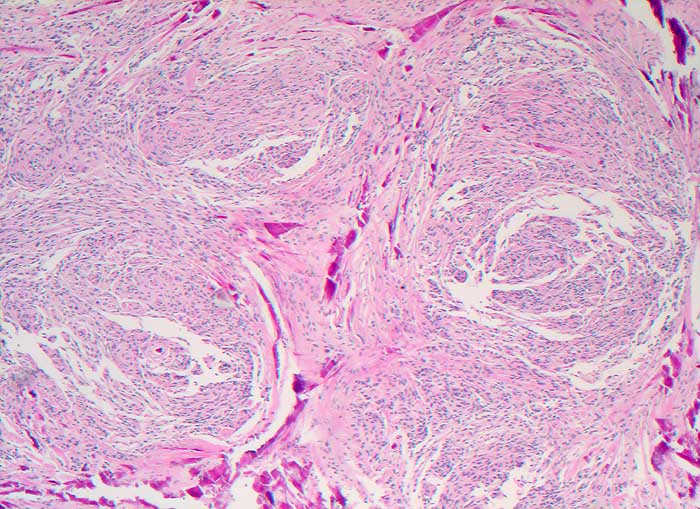

PathoPic ID 5631 - Meningeom

Meningeom

benigner Tumor

Rückenmark

Nervensystem

Deutliche Wirbelbildungen und ausgedehnte Verkalkungen

Spinaler Tumor Th 12.

Am ehesten handelt es sich um einen transitionalen Typ mit häufigem Nachweis von Wirbelbildungen und Psammomkörperchen.

Histologie

50